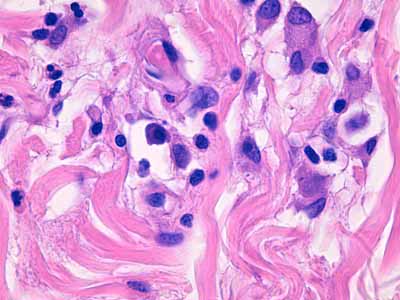

Photo 14 (Hémalun-Eosine X1000 objectif à immersion) : Vue au fort

grossissement de l’infiltrat inflammatoire dermique péri-vasculaire, formé de macrophages,

de plasmocytes et de granulocytes éosinophiles. Certains macrophages contiennent

un élément ovalaire de quelques micromètres de diamètre, discrètement bipolaire, dont

la silhouette apparaît compatible avec un parasite protozoaire et notamment avec le genre Leishmania.

Légendes de la Photo 14 :

- Étoile vertes : granulocytes éosinophiles

- Étoiles turquoises : plasmocytes

- Cercles jaunes : macrophages

- Pointe de flèche jaune : noyau de fibrocyte

- Flèche jaune : faisceau de fibres de collagène

- Étoiles rouges : un élément figuré est parfois visible dans le cytoplasme de macrophages, celui ciblé par l’étoile la plus épaisse apparaît nettement “bi-polaire” avec un pôle sombre (le noyau) et un pôle pâle (le cytoplasme) suggérant une forme amastigote de Leishmanie.